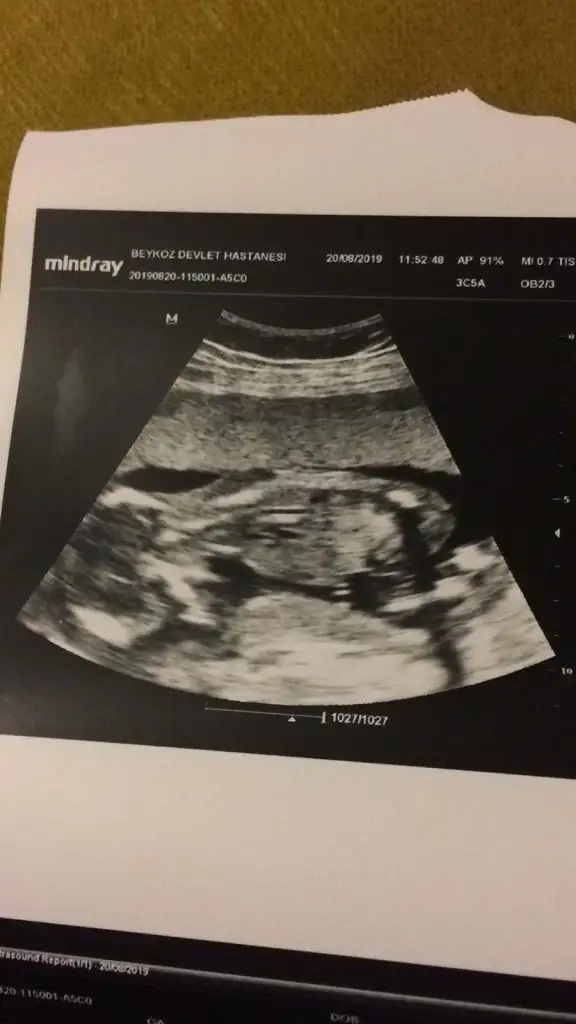

Erkek diyorumMerhaba banada bi tahmin yaparmısınız lütfen

Yine erkek diyorumEvet siz de erkek demiştiniz![]()

Bana kiz gibi geldi canimMerhaba bzimde cinsiyetimize bakarmısıminız

Yine erkek diyorum![]()